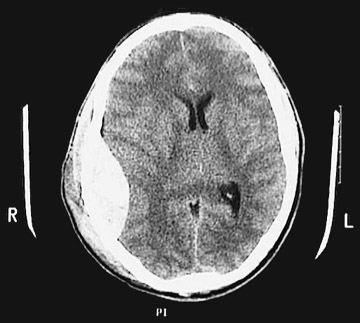

A 20-year-old student fell off his bike directly on his head on the way to school. He was not wearing a helmet and was seen unconscious when paramedics arrived. At the emergency room his pulse and blood pressure were weak, and there was no sign of scalp laceration. The doctor examined his pupils and found that the right was fixed and dilated and would not react to light. A CT scanwas ordered immediately, and a right-sided epidural hematoma was revealed. The patient was moved to the intensive care unit, and an emergency evacuation of the hematoma was planned.

- What is the source of the epidural hematoma

?

It is usually the middle meningeal artery or vein.- Why was there a dilated pupil on the hematoma side

The pupil dilates due to paralysis of the sphincter pupillae muscle due to loss of parasympathetic fibers carried by the oculomotor nerve and the resultant unopposed action of the intact dilator pupillae muscle (sympathetic innervation). This muscle gets paralyzed when the oculomotor nerve (CN III) is injured by pressure from a hematoma, usually epidural.- What are the structures that lie in the lateral wall of the cavernous sinus?